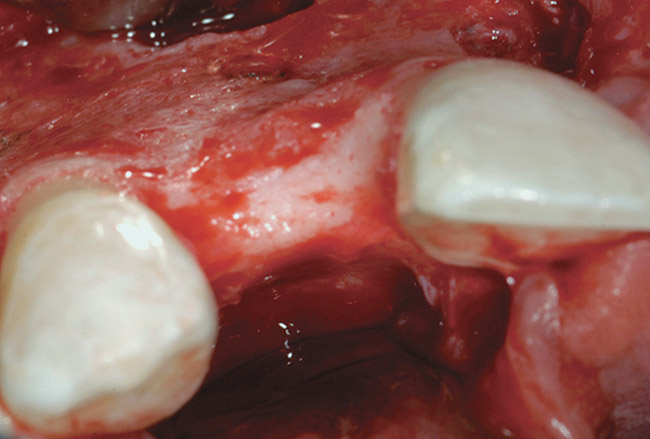

A 72-year-old man was referred for removal of failing maxillary right posterior implants (Figure 19). The treatment plan included removal of three implants with simultaneous bone augmentation and replacement implants for implant-supported fixed bridgework. Implant removal and bone grafting with rhPDGF (Gem 21®, Osteohealth, www.osteohealth.com) and allograft (MinerOss) and xenograft (BioOss®, Geistlick, www.geistlickonline.com) were used along with titanium mesh for space maintenance (Figure 20, Figure 21 and Figure 22). Six months later, mesh removal revealed type I bone allowing for placement of three implants (Figure 23 and Figure 24).

Figure 23  Trephinated core biopsy obtained at 5 months.

Figure 23

Figure 24  Histology: Note active osteocytes with new bone formation.

Figure 24